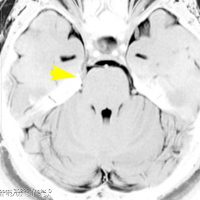

これは1989年に50歳で発症した左三叉神経痛の女性のMRIです。赤いのが類表皮のう胞という良性腫瘍で,黄色く塗ったのが左三叉神経です。腫瘍による圧迫で三叉神経がゆがんでいるのがよく解ります。2010年まで20年間,ほんの少しのカルバマゼピン(テグレトール)の服用で我慢できました。腫瘍は20年の間にゆっくり大きくなって,一時期は左の顔面けいれんもありました。2010年になって眼球運動障害による複視(ものが2重に見える)という症状が出て,年齢も70歳を越えたので開頭手術で腫瘍を摘出しました。術後は目の動きも正常になって三叉神経痛も消失しました。でも,類表皮のう胞の手術はリスクもあって簡単なものではありませんから,手術をすぐに勧める場合と,この患者さんの様にながーく経過を見る場合があります。判断は難しいものです。